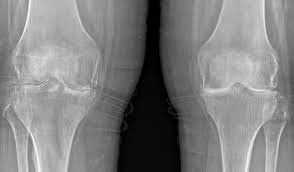

Knee Conditions GET IN TOUCH Knee Arthritis Meniscal Tears ACL Tears Knee Instability The Painful Or Failing Knee Replacement Knee Arthritis Learn MOre Meniscal Tears Learn MOre ACL Tears Learn MOre Knee Instability Learn MOre The Painful Or Failing Knee Replacement Learn MOre KNEE SURGERY OUR SERVICES If joint pain or injury is affecting your daily life, Dr Paterson is here to support your recovery with individualised, evidence-based care. Knee Arthritis Learn MOre Meniscal Tears Learn MOre ACL Tears Learn MOre Knee Instability Learn MOre The Painful Or Failing Knee Replacement Learn MOre OTHER TREATMENT OPTIONS